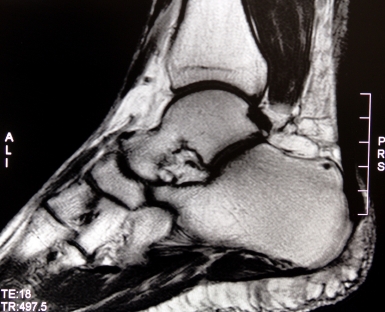

Проводится изучение истории болезни и медицинский осмотр. Часто в анамнезе - занятие спортом, плоскостопие, ношение высоких каблуков. Диагноз можно установить уже при осмотре, но для уточнения диагноза проводится: рентгенография голеностопного сустава, УЗИ, магнитно-резонансная томография.

Медицинские процедуры, проводимые при заболевании тендинит (воспаление) ахиллова сухожилия: Рентген, УЗИ, Магнитно-резонансная томография